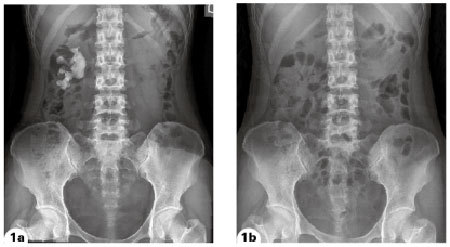

Figure 1a. Pre-PCNL Figure 1b. Post-PCNL |